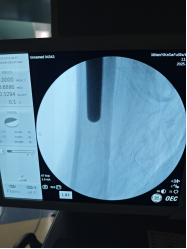

8月8日,一场精密的"生命保卫战"打响。由骨科尹一然教授领衔,联合麻醉科、心血管内科、肾内科等专家制定方案:既要取出刺入盆腔的钢钉,又要解决髋臼缺损和骨量流失难题,还要确保新关节稳固。

手术台上,团队创新采用"双重修复"策略——

精准清障

先小心翼翼取出嵌在盆腔的钢钉,避免损伤血管;

巧补缺损

将患者自身修剪后的股骨头骨质填补到髋臼破损处,重建"地基";

稳固支撑

植入特制加长股骨柄假体,像"钢筋"一样牢牢固定新关节。

3小时后,手术圆满成功! 术中出血量控制理想,老人生命体征平稳。更让人惊喜的是,术后第二天邱婆婆就能自主屈伸双腿,疼痛明显缓解。"没想到还能再站起来!"家属紧握医生的手连连道谢。